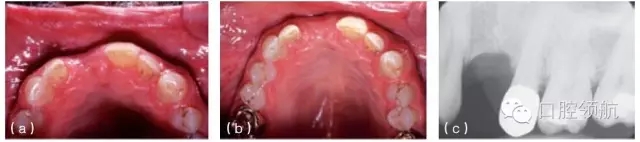

圖10.2 (a)治療前缺牙區(qū)的切面觀,可見唇側(cè)有骨缺損。(b)缺牙區(qū)植骨后的切面觀,可見唇側(cè)牙槽嵴厚度增加。(c)治療前X線片顯示上頜第一前磨牙的拔牙區(qū)有較大骨缺損。(d)植骨后植入種植體。(e)由于種植體植入前對骨缺損區(qū)進(jìn)行植骨,第一前磨牙的冠在高度和頰側(cè)面的位置都接近正常。